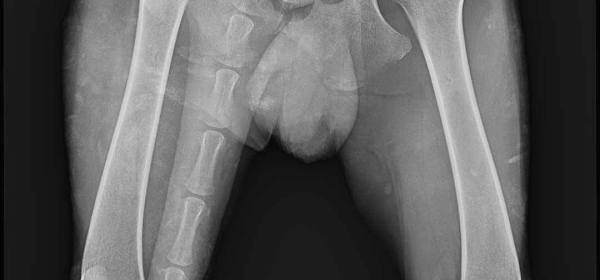

Hani hat die Röntgenaufnahmen hinter sich gebracht und sich von der Sedierung erholt. Leider ist die erste Prognose alles andere als erfreulich und hat uns